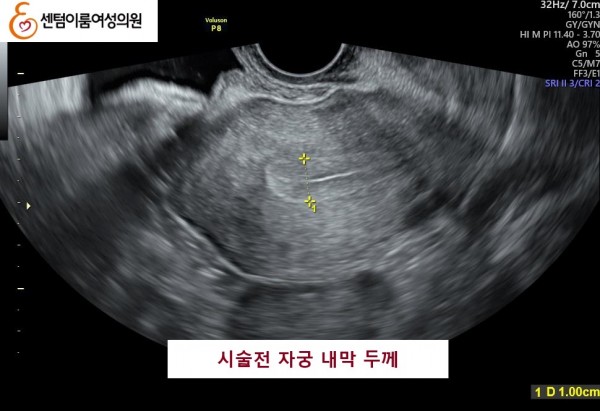

2024.12월 본원 내원 전 타병원에서 다수의 시술 경험이 있으셨습니다.

40세 이상 고령 연령은 염색체 비정상 난자 비율이 높아 고난도 난임의 대표적인 사례입니다.

꾸준한 식생활 개선과 약물 치료를 받으시고 임신에 성공 하셨습니다.